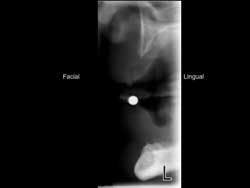

Radiographs that show only two–dimensional, panoramic, periapical, or bitewing views do not show the density of bone in a facial–lingual dimension. Tomographic or cone–beam radiographs are strongly recommended before placing any diameter of implant to allow visualization of bone characteristics in a facial–lingual dimension. These types of radiographs are available in most communities if you do not have that capability yourself. If the bone appears to be porous in any dimension, conventional–diameter implants are a better choice than SDIs.

Patients having the previously described bone characteristics — i.e., at least 3 or more mm of bone in a facial–lingual dimension and at least 10 mm of bone in an occlusal–apical dimension — are excellent candidates for SDIs (see Fig. 1).